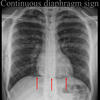

Continuoius diaphragm sign

Pneumomediastinum